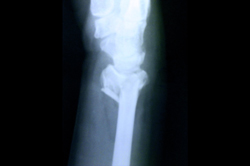

Lower Radius